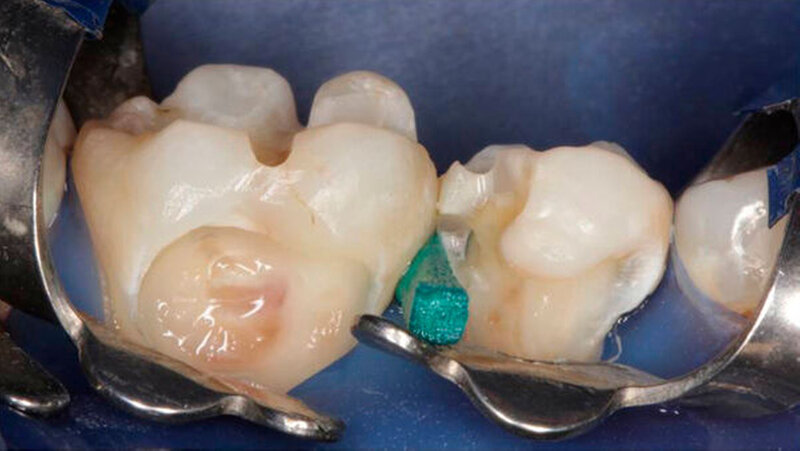

Die Behandlung umfasste zwei Termine (erster: Zahn 46 und 45, zweiter: Zahn 43 und 44). Zur Entfernung der alten Füllungen dienten ein runder und ein zylindrischer Diamantbohrer sowie langsam laufende Hartmetallbohrer und zur Feinbearbeitung der Kavitäten ein Ultraschallinstrument. Nach selektiver Schmelzätzung applizierte man das Adhäsiv XP BOND®. Das Dentin wurde durch SDR ® ersetzt. Dann wurden mit ceram.x one® d3 und e2 jeweils der Rest der Kavität und die Höcker restauriert. Finiert und poliert wurde mit dem Soflex Poliersystem.

Die Restaurationen erfolgten minimal-invasiv. Durch Wiederherstellung der natürlichen Morphologie wurde für eine stabile Okklusion gesorgt. Auch bei der Kontrolle nach 9 Monaten machten die Füllungen morphologisch und farblich einen guten Eindruck. Ästhetik und Funktion gingen Hand in Hand.